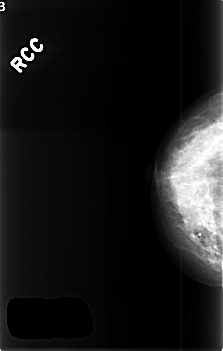

RIGHT_CC LINES 4552 PIXELS_PER_LINE 2888 BITS_PER_PIXEL 12 RESOLUTION 50 NON_OVERLAY